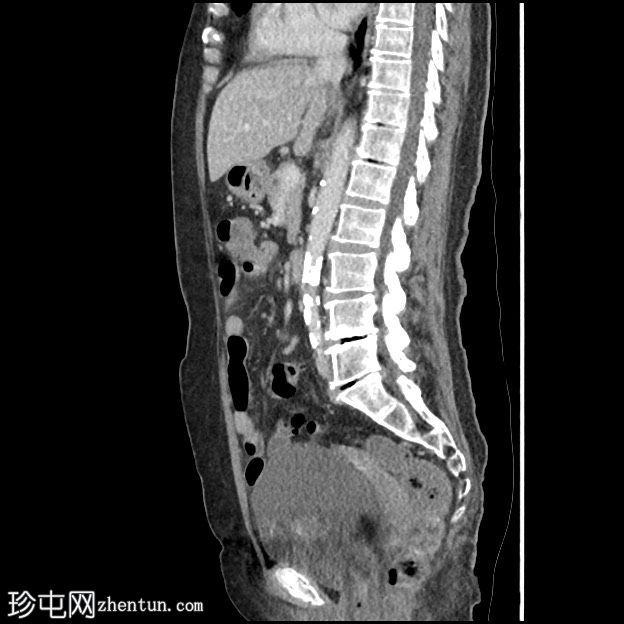

矢状 C+ 门静脉期

小肠系膜内急性炎症过程,脂肪密度增加,肠系膜充血。多个小囊状游离气体表明肠道穿孔。小体积聚液体,边缘增强。相邻小肠可能继发(反应性)增厚。小肠对系膜边界出现多个憩室。肠系膜血管正常增强。无并发症的结肠憩室病。

发现符合急性小肠憩室炎伴局部穿孔。

在轻度急性乙状结肠憩室炎发作期间的先前影像显示,空肠系膜边界出现大量大型充满气体的憩室。